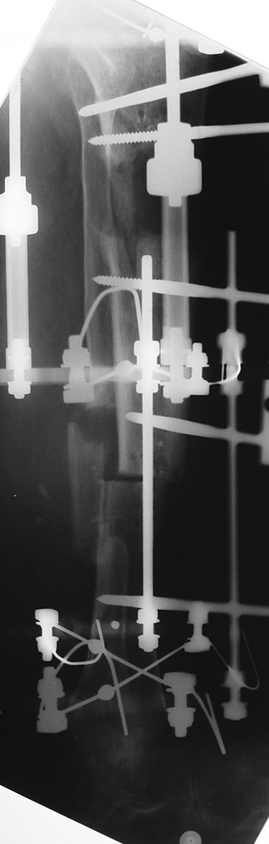

Uygun radikal debridman tüm nekrotik kemik ve yumuşak dokuların çıkartılmasını gerektirir, ve sıklıkla uzuvda instabiliteye neden olur. Kalan kemik ve yumuşak doku defektinin bir şekilde fiksasyonu ve rekonstrüksiyonu gereklidir. İlizarov’un ortaya koyduğu distraksiyon osteogenezi yöntemi, kaynamanın elde edilmesi, deformitenin düzeltilmesi, bacak boy eşitsizliğinin giderilmesi ve segmental defektlerin rekonstrükte edilmesi için başarıyla kullanılmaktadır.

Eksternal fiksatör ile geçen süre (eksternal fiksasyon indeksi), gereken distraksiyon miktarına bağlıdır ve bu süre boyunca bazı komplikasyonlarla karşılaşılabilir. Distraksiyon dönemi sona erdikten sonra, distraksiyon süresinin iki katını aşan konsolidasyon döneminde hastalar eksternal fiksatörü zorlukla tolere edebilirler. Yeterli konsolidasyon sağlanmadan eksternal fiksatör çıkartılırsa ise kırıklar, deformite ve kısalık oluşabilir. Hastanın fiksatör ile birlikte geçirdiği sürenin azaltılması ve böylece hasta konforunun ve aktivite düzeyinin arttırılması için intramedüller çivi üzerinden uzatma yöntemi uygulanmaktadır. Bu yöntemde distraksiyon dönemi sona erdiğinde kemiğin içindeki çivi statik olarak kilitlenmekte ve eksternal fiksatör çıkartılmaktadır. Stabilizasyon intramedüller çivi tarafından sağlandıktan sonra konsolidasyon dönemi gerçekleşmektedir. Bu şekilde hem eksternal fiksatörün uzun süre kalmasından hem de erken çıkartılmasından kaynaklanan komplikasyonların önüne geçilmektedir.